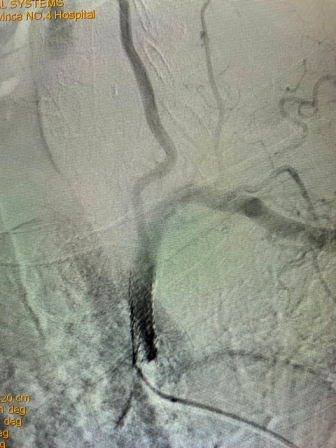

(术前造影) (手术后造影)

该患者是一位79岁老年男性,门诊以“头晕伴走路不稳”主诉入院。既往有高血压、冠心病PCT术后、慢阻肺病史。入院后完善相关检查,行B超检查考虑“左侧锁骨下动脉盗血”,进一步检查DSA全脑血管造影术时发现:“左侧锁骨下动脉闭塞,左侧锁骨下动脉盗血”。为解决患者疾病痛苦及改善其生活质量,神经内科任主任刘蔚玲主持召集专家团队讨论并精心安排,在客座教授刘亚民周密指导下,由神经内科侯有荣副主任医师、孟军鹏主治医师、赵荣健等骨干医生,通过开通闭塞处血管、球囊扩张后置入支架,手术顺利,术后造影显示患者左侧锁骨下动脉血流再通,锁骨下动脉盗血现象消失,血管再开通,患者术后无明显不适、后循环缺血症状消失。手术极大地改善了其生活质量,同时也有效地预防了严重的脑卒中事件的发生。

此例高龄患者、锁骨下动脉闭塞后再通、同时联合椎动脉狭窄病变的同期治疗,其手术复杂、难度大、风险高,神经介入手术创伤小,恢复快,效果立竿见影,其闭塞血管的顺利开通为预防其以后再发生脑梗死奠定了极为重要的基础。该例手术成功完成,再次标志着六合彩生肖神经内科(卒中中心)神经介入技术水平更上一层新台阶。(采编 党委宣传部)